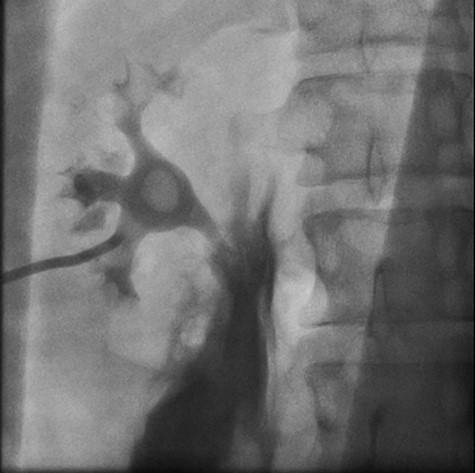

Left retrograde cystoscopy exhibiting extravasation of contrast.

Cystoscopy with retrograde pyelogram was performed by the urology team and this showed total disruption of the UPJ bilaterally with extravasation of contrast (Figs 3 and 4). She underwent bilateral interventional radiology nephrostomy tube placement. The definitive repair was planned for after pregnancy, but she required tube changes every 6 weeks. There was no fetal distress during her stay. She recovered well and was discharged after 5 days.